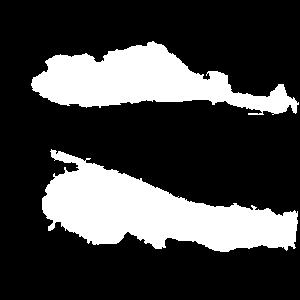

In order for the LDI scans to be comparable with BAM binary segmentations, a number of processing steps were conducted. LDI scans can have different sizes, scales, and cropping in comparison to their corresponding burn images. As BAM uses the burn 2D colour images as the input for creating the binary burn segmentations, the LDI scans were first aligned with their corresponding burn images and converted into the same size as those images. Once the LDI scans are aligned with input images and their colors are processed in order to create binary masks, quantitative comparisons with BAM segmentations were conducted. For this purpose, we utilised the manual segmentations of burn areas from burn images validated by clinicians.

Moreover, as discussed later, it was discovered that the LDI scan color palette, which demonstrates different healing potentials, would classify uninjured areas and background noise in the image as burns with poor blood flow. In a clinical setting, this misclassification does not lead to a serious issue as scans are reviewed by clinicians who can easily differentiate between normal skin/background and burn area. However, since the processing of LDI scans is conducted by computer vision, this issue needed to be resolved. This was addressed by removing the non-burn areas from the LDI scans before processing LDI scans by multiplying the aligned LDI scans with the manual segmentations of burn areas resulting in LDI scans that show various healing potentials (or various degrees of burn) in the burn area only.

Once the heatmaps with the highest correlation coefficients are selected, these high-resolution visualizations are utilized as the input to make binary segmentation masks as illustrated in Figure 4(i). The generation of masks uses Gaussian components of the maps to find thresholds (Figure 4(ii)) and subsequently uses the highest Intersection-Over-Union (IOU) values (Figure 4(iii)) between the binary masks generated and the Grad-CAM to select the final mask. The generated binary segmentation mask lastly undergoes a post-processing step in order to filter out the noise/false positive regions and produce the final BAM mask (Figure 4(iv)), which can be used for super-positioning on the input image (Figure 2b).